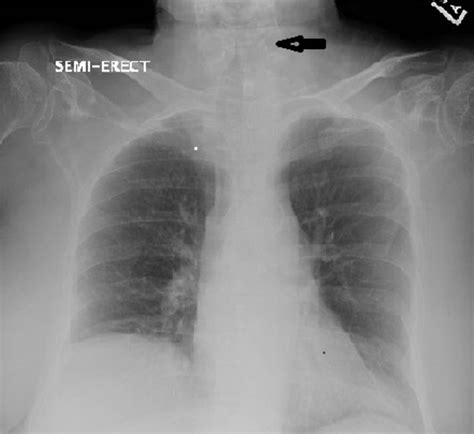

• Order diagnostic tests, such as a chest X-ray or blood tests, if necessary.